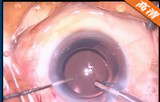

白内障超声乳化吸除联合爱尔康 ReSTOR+3多焦人工晶体植入术

该手术在10点钟位透明角膜主切口制作,前房注入粘弹剂,2点钟位侧切口制作,撕囊镊做连续环形撕囊,做水分离和水分层 ,预吸晶状体皮质 ,超乳劈核法劈核,并逐块乳化吸除核块以及皮质,I/A吸除残留的皮质并对后囊膜进行抛光,前房及囊袋注入粘弹剂,植入爱尔康多焦人工晶状体,吸除前房以及人工晶状体后的粘弹剂。